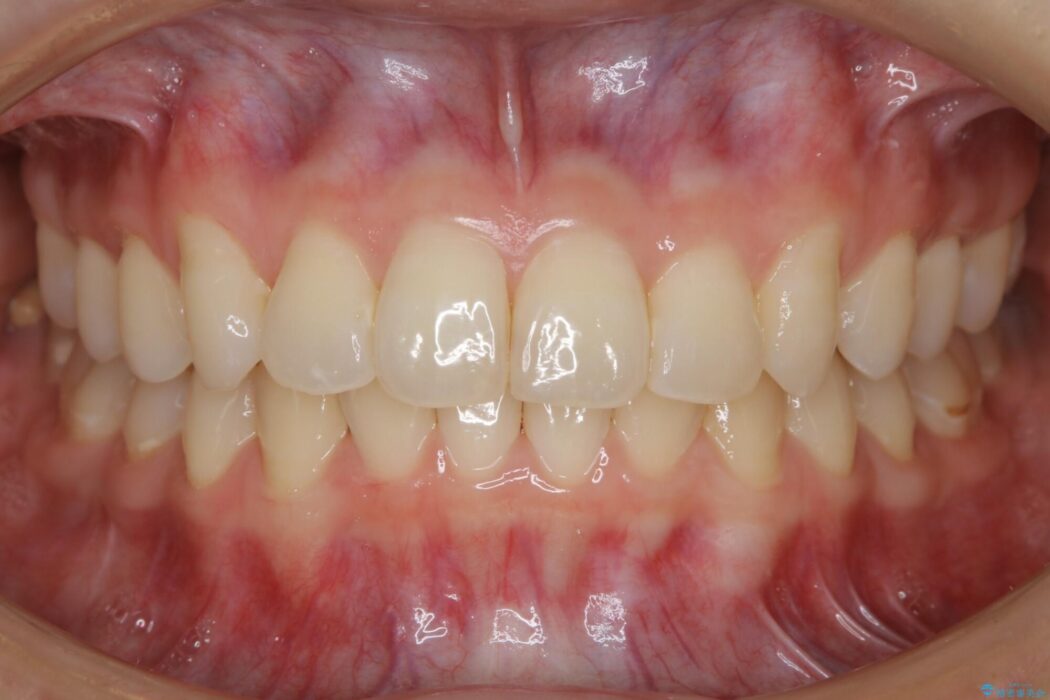

【20代女性】ブライダルに向けた矯正できれいなスマイルラインへ

笑った時に見える歯並びをきれいにしたいとの主訴で来院されました。

ガタつきの度合いから抜歯は不要と判断しましたので、マイクロインプラントを用いて歯全体を遠心移動させていくことでねじれや噛み合わせのズレを改善していく計画を立てました。